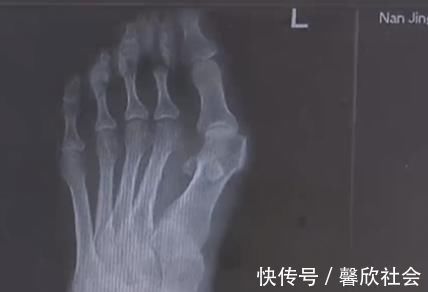

【 女性 爱穿高跟鞋的女性一定要小心,拇指外翻堪比“裹脚”!不可忽视】穿高跟鞋是不少女生出门前的必备,今年32岁的王女士十几年前就有了穿高跟鞋的习惯。然而就在最近,自己的脚趾出现了惊人的变化,两边的大脚趾一侧渐渐突起了一个硬疙瘩,走路一久就疼痛不已。

由于高跟鞋的挤压,王女士的左脚大脚趾变成了两个脚趾,随着时间的推移,大脚趾一侧又多了一个 \\'\\'拐\\'\\',现在只能通过手术来缓解症状。除了鞋子不当,遗传和疾病因素也是造成拇指外翻的原因,70 岁的高女士患风湿病,脚也发生了接近 60 度的严重变形。